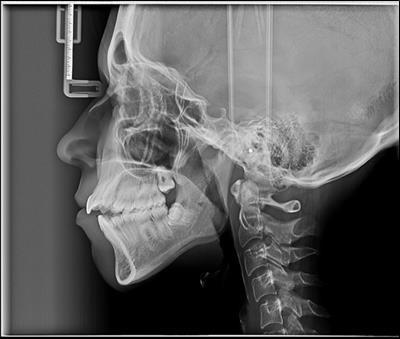

The cephalometric analysis indicated that she had a skeletal class II profile ,proclination of the maxillary central incisor ,high mandibular plane angle that contributed to the class II skeletal relationship and increased lower facial height.

Figure 2.Pretreatment cephalometric film

Pretreatment cephalometric film